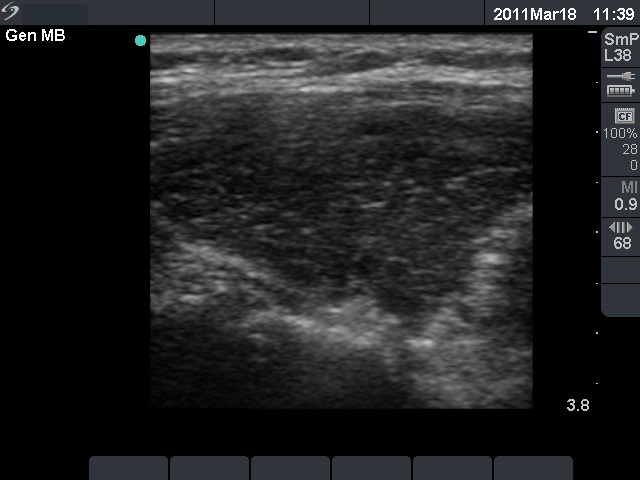

Chronic lymphocytic thyroiditis - Figure 1. Ultrasound patterns according to the degree of hypoechogenicity.

Diffuse hypoechogenicity is the most important sonographic sign of Hashimoto's thyroiditis. The degree of hypoechogenicity varies greatly, and correlates relatively well with aTPO level. We have to notice the hypoechogenicity in a euthyroid patient in order to consider the possibility of the underlying autoimmune thyroid disease and therefore to give the chance to recognize hypothyroidism later.

A moderately hypoechogenic thyroid is presented with small hypoechogenic areas.